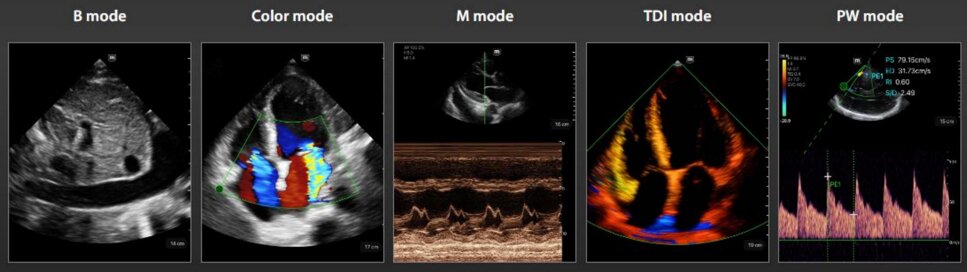

- Sonde a frequenza variabile,Color Doppler,Pulsed Wave,Power Doppler.

- Armonica di tessuto,Spacial Compound ,Connessione WiFi e USB ,velocità wireless elevato.

- Sonde a frequenza variabile,Color Doppler,Pulsed Wave,Power Doppler.

- Armonica di tessuto,Spacial Compound ,Connessione WiFi e USB ,velocità wireless elevato.